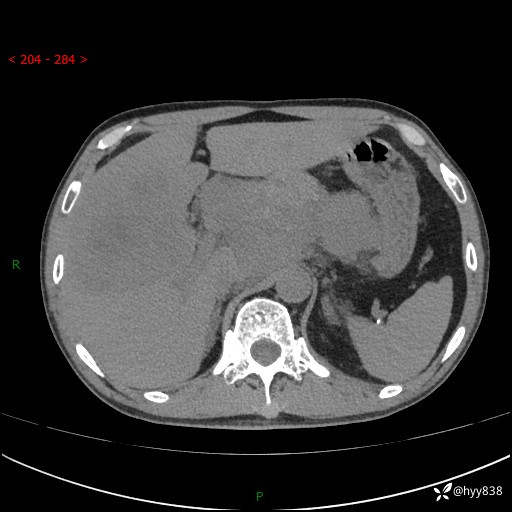

56岁/男,持续性干咳1周余,外院超声发现肝占位,少见病例---结果公布~

现病史:患者1周前无明显诱因出现刺激性干咳,伴食欲减退,无痰,无发热、头晕头痛、恶心呕吐、腹痛腹泻、胸闷喘气、厌油、巩膜黄染等不适,于当地诊所就诊并予以输液治疗,具体不详,患者诉干咳症状稍微好转,现患者为行进一步检查于当地第五人民医院就诊,肝脏彩超提示“肝占位性病变”,遂转入我院门诊就诊,经检查后门诊以“肝占位性病变”收入我科。 患者自起病以来精神、食欲如上述、睡眠一般,大小便正常,近半月内体重降低20余斤,体力无明显下降。

上腹部CT平扫+增强(两期)